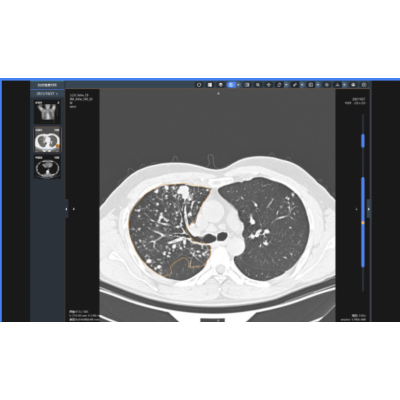

肺结节影像辅助分类诊断

精准识别、分割肺部各类结节灶,输出病灶定位、体积、倍增、密度、形态、征象等多元化参数,进行基于人工智能深度学习的病灶良恶性诊断,肺癌结节灶实现定性诊断。提供随诊复查功能系统,实现多次检查间病灶精准匹配,定量分析,帮助更方便地疾病监测、疗效评估。